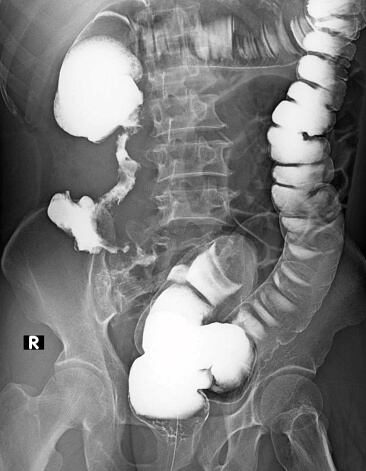

Los estudios que han hecho frente a este procedimiento han arrojado que un enema de café podría causar efectos adversos, como colitis, que consiste en una inflamación del revestimiento del colón, y proctitis, una inflamación del recto.

El gastroenterólogo indica que: “la colitis puede causar dolor o hemorragia y, si el líquido del enema está caliente, también puede provocar quemaduras rectales”.